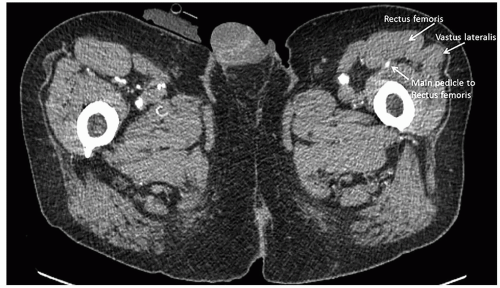

The major pedicle is a medial branch from the lateral femoral circumflex artery (FIG 1C). The branch to the rectus femoris muscle emerges 1 to 2.5 cm distal to where the lateral femoral circumflex artery splits from the profunda femoris artery. The pedicle tends to enter the muscle on its deep and lateral surface. After sending a branch to the rectus femoris muscle, the lateral femoral circumflex neurovascular bundle continues inferiorly, traveling in the septum between the vastus lateralis and rectus femoris muscle, to supply the tissue of the anterolateral thigh flap.

The muscle is bordered by the vastus medialis medially, the vastus lateralis laterally, and the vastus intermedius on its deep surface. The sartorius muscle crosses obliquely over the rectus femoris muscle proximally.